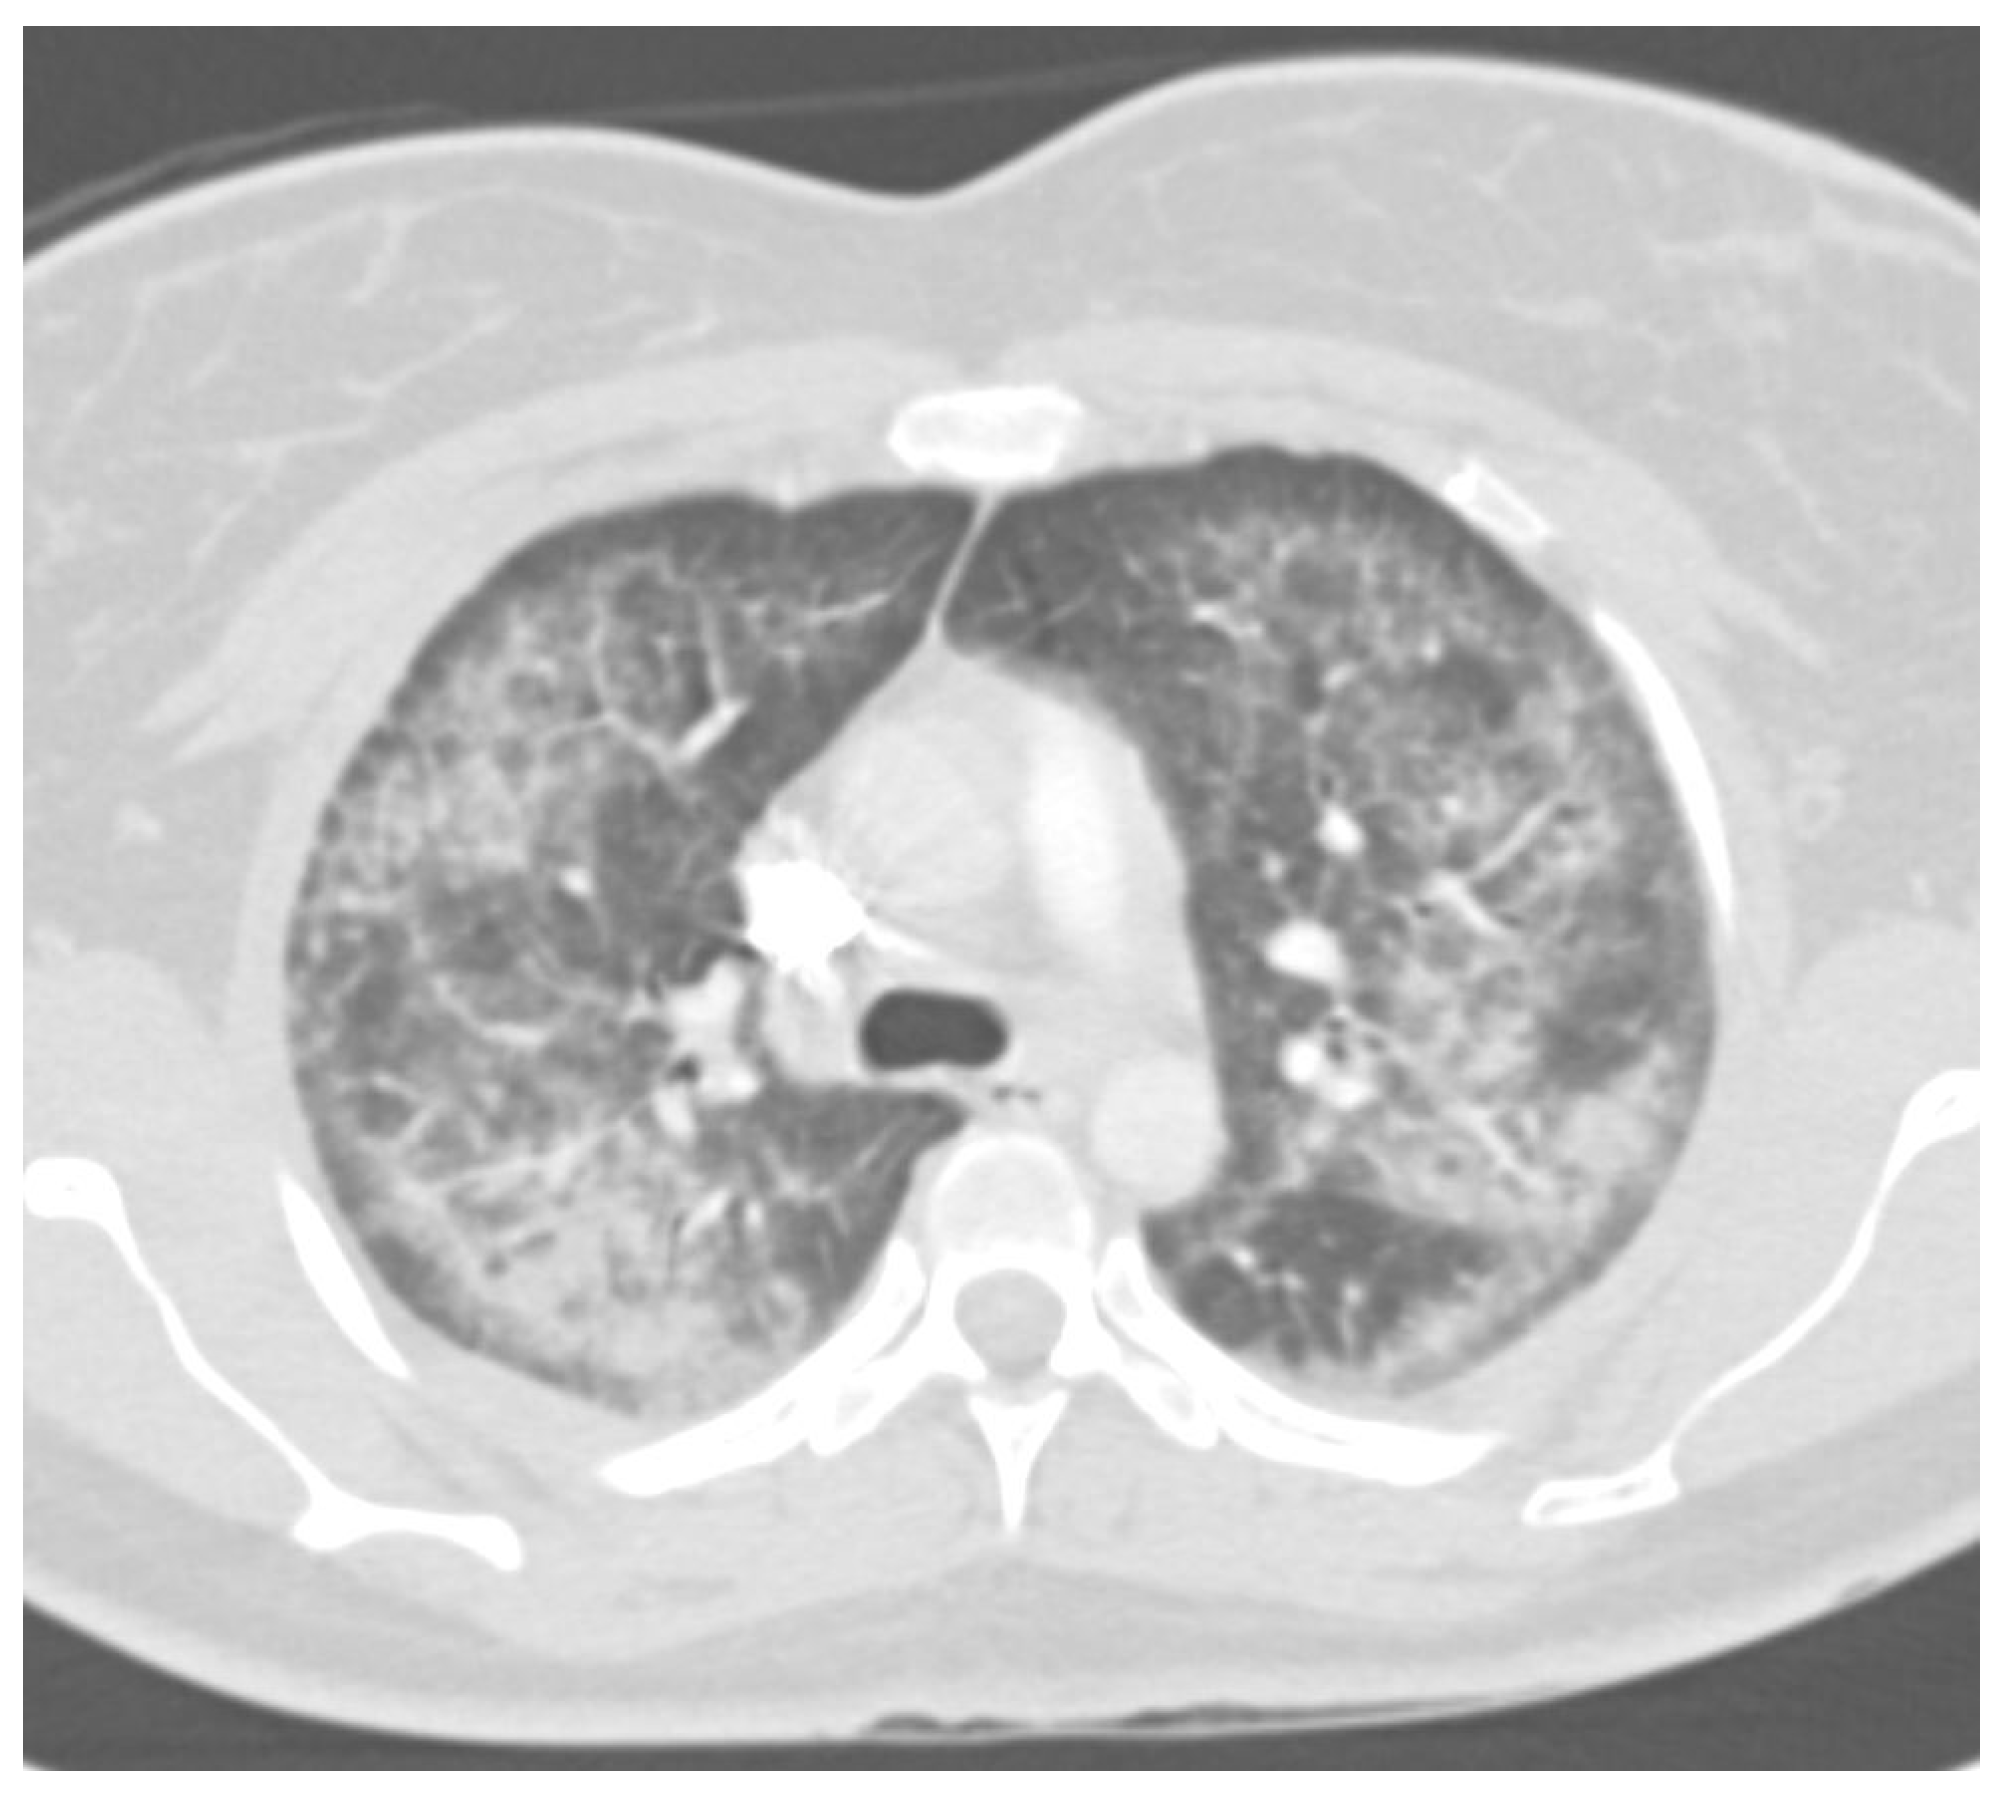

- Discuss the known long-term consequences and ongoing research directions related to EVALI.

7. Radiology

- Kligerman, S.; Raptis, C.; Larsen, B.; Henry, T.S.; Caporale, A.; Tazelaar, H.; Schiebler, M.L.; Wehrli, F.W.; Klein, J.S.; Kanne, J. Radiologic, Pathologic, Clinical, and Physiologic Findings of Electronic Cigarette or Vaping Product Use–Associated Lung Injury (EVALI): Evolving Knowledge and Remaining Questions. Radiology 2020, 294, 491–505. [Google Scholar] [CrossRef] [PubMed]

- Kligerman, S.J.; Kay, F.U.; Raptis, C.A.; Henry, T.S.; Sechrist, J.W.; Walker, C.M.; Vargas, D.; Filev, P.D.; Chung, M.S.; Digumarthy, S.R.; et al. CT Findings and Patterns of E-Cigarette or Vaping Product Use-Associated Lung Injury. Chest 2021, 160, 1492–1511. [Google Scholar] [CrossRef] [PubMed]